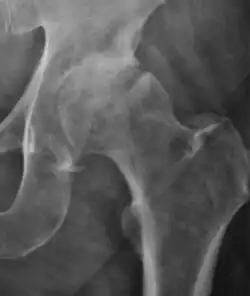

Projectional radiography ("X-ray") is currently useful not only in older people in whom osteoarthritis of the hip is suspected but also in younger people without osteoarthritis, who are being evaluated for femoroacetabular impingement (FAI) or hip dysplasia.[1]

Plain radiography allows us to categorize the hip as normal or dysplastic or with impingement signs (pincer, cam, or a combination of both). Besides these, pathologic processes like osteoarthritis, inflammatory diseases, infection, or tumors can also be identified (Figure 1).[1]

Figure 1.

-

Radiography in normal hip

X-ray in pincer impingement type of hip dysplasia

X-ray of cam

Hip in osteoarthritis

Septic arthritis

In adults, one of the main indications for radiographs is the detection of osteoarthritic changes (Figure 1(e)). Nevertheless, radiographs usually detect advanced osteoarthritis that can be graded according to the Tönnis classifications. The grading system ranges from 0 to 3, where 0 shows no sign of osteoarthritis. Intermediate grade 1 shows mild sclerosis of the head and acetabulum, slight joint space narrowing, and marginal osteophyte lipping. Grade 2 presents with small cysts in the femoral head or acetabulum, moderate joint space narrowing, and moderate loss of sphericity of the femoral head. Grade 3 is the severest form of osteoarthritis, which manifests as severe narrowing of the joint space, large subchondral cyst with productive bone changes that may lead to deformity of the bone components of the joint, while secondary osteoarthritis due to calcium pyrophosphate deposition can be diagnosed when calcification of hyaline cartilage and fibrocartilage is detected.[1]

There are other pathological conditions that can affect the hip joint and radiographs help to make the appropriate diagnosis. Acute bacterial septic arthritis can be diagnosed by radiographs when a fast regional osteoporosis and destructive monoarticular process develops (Figure 1(f)). In case of tuberculous or brucella arthritis it is manifested as a slow progressive process, and diagnosis may be delayed.[1]